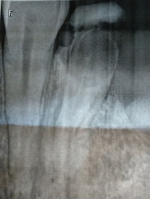

Оценить необходимость удаления зуба можно по рентгеновскому снимку. Вам необходимо сделать прицельный рентгеновский снимок и обратиться к стоматологу-терапевту. Если корни зуба пролечены хорошо, не воспаления в области верхушки корня и сам корень целый, то возможно ортопедическое восстановление зуба (штифт + вкладка, штифт + коронка). Конечно, если корень в плохом состоянии, то зуб удалят. Бояться не стоит, современные анестетики очень мощные и при должном проведении анестезии пациенты ничего не чувствуют.

Необходим осмотр и прицельный рентгеновский снимок зуба. 1) Как правило, стенка зуба скалывается, когда жевательный зуб ранее был лечен и восстановлен пломбой больших размеров. И при жевании тонкая стенка не выдерживает нагрузки и скалывается. 2) Если скол произошёл ниже уровня десны – это показание к удалению зуба и восстановлению дефекта имплантом или мостовидным протезом. Если выше уровня десны, тогда эндодонтическое лечение зуба и восстановление его вкладкой и коронкой. Проконсультируйтесь очно со стоматологом-терапевтом.

Необходим прицельный рентгеновский снимок зуба и осмотр. Скорее всего, в зубе возникло такое осложнение как периодонтит. Воспалительный процесс уже в костной ткани за верхушкой корня зуба. Коронковая часть зуба поражена кариесом, есть скол стенки зуба под десной, мало здоровых твердых тканей зуба, много деминерализованных тканей, поэтому такой зуб подлежит удалению. Проконсультируйтесь со стоматологом-хирургом. После удавления, дефект следует заместить имплантом или мостовидным протезом.

Вообще не следует переживать. Стоматология сейчас на очень высоком уровне развития, применяются сильнейшие обезболивающие. 1) Исход лечения зависит от клинического осмотра и рентгеновского снимка. Если на рентгенограмме корни зуба в хорошем состоянии, без патологического воспаления, то будет проведена чистка и пломбирование каналов, а клиническую коронку восстановят по показаниям композитом, штифт + композит или ортопедической коронкой. 2) Если корни зуба в плохом состоянии, то такой зуб по удаление.

Необходимо сделать рентгеновский снимок и оценить состояние корня. Если отсутствуют воспалительный деструктивный процессы, а также перелом или трещина корня, то анатомическую форму зуба можно восстановить ортопедической коронкой.